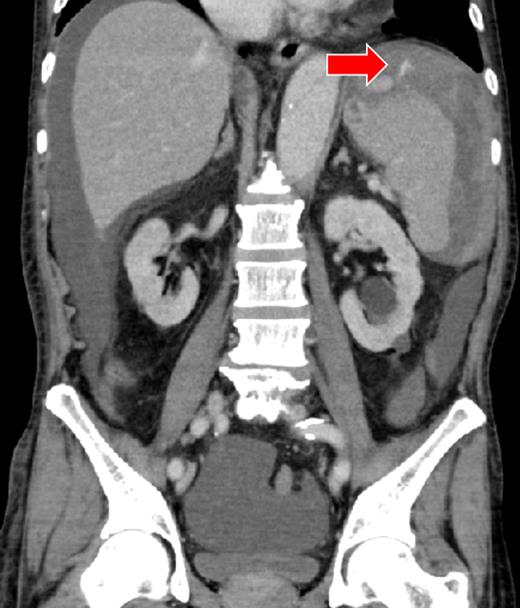

A 66-year-old man presented after suffering sudden hypotension and abdominal distension, followed by a rapid and progressive anemia. After arriving at hospital, he collapsed and went into cardiac arrest. Return of spontaneous circulation occurred after 36 min of cardiopulmonary resuscitation and rapid blood transfusion. Abdominal contrast-enhanced computed tomography (CECT) revealed a large hematoma around the spleen and liver, in paracolic gutters and the pelvis with active arterial extravasation and apparent capsular disruption (Fig. 1). He was transferred to our hospital for definitive, emergency hemostasis. At admission, his systolic blood pressure (BP) was 90 mmHg; heart rate (HR), 80 bpm; hemoglobin (Hb) level, 6.7 g/dl; hematocrit (Ht), 19.0%; prothrombin time-international normalized ratio (PT-INR), 2.16 and activated partial thromboplastin time (APTT), 63.9 s (under massive transfusion). He was currently on warfarin therapy for anticoagulation following a total aortic arch replacement including aortic valve replacement at the age of 60. He presented with no history of trauma, and Moraxella catarrhalis had been detected in a blood culture taken on initial presentation. We made a diagnosis of ASR secondary to infection exacerbated by anticoagulation therapy. We first planned to perform a splenectomy as a definitive hemostatic treatment. However, his transfusion requirement was massive and the risk of significantly worsened hemorrhage during any operative procedure was increased by his iatrogenic coagulopathy. After discussion with surgery team and interventional radiology (IR) team, transient occlusion of the splenic artery using a microballoon catheter was performed (LOGOS, Piolax, Inc., Kanagawa, Japan; arrival to occlusion, 90 min; arrival to angiography suite, 60 min; procedure time to occlusion, 15 min; Fig. 2). Soon after balloon occlusion, the patient's hemodynamic state improved and his anemia stabilized. Perioperatively, 6 units of red cell concentrate (RCC) and 10 units of fresh frozen plasma (FFP) were transfused. The patient's coagulopathy improved on hospital Day 2 (Ht, 25%; PT-INR, 1.35 and APTT, 33.5 s) and was taken to the operating theater for open splenectomy. The spleen was swollen and capsular rupture was indeed identified, but there was no finding of a solid tumor or abscess formation. Bone marrow aspiration did not reveal any evidence of a hematological disorder. There was no subsequent hemorrhage postoperatively. He was extubated on Day 4, and was discharged from the ICU on Day 6. The patient was transferred to another hospital on Day 25 without residual deficits or complications from his cardiac arrest.

There was a massive hematoma in the peritoneum surrounding the spleen and the liver, and extending into the paracolic gutter and the pelvic cavity. The capsule of the spleen was disrupted, and active arterial extravasation can be seen around the spleen (arrow).